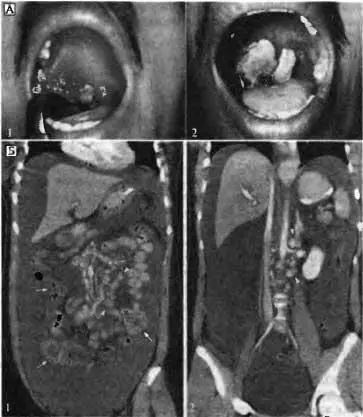

При употреблении в пищу сьшого мяса или мясопродуктов иногда у людей наблюдается поражение верхних отделов пищевари гельного тракта — орально-фарингеальная (ротоглоточная) разновидность сибирской язвы у человека. При этой разновидности сибирской язвы инкубационный период составляет в среднем 42 ч (диапазон от 2 до 144 ч). Средний период от момента появления клинических симптомов до госпитализации — 3,5 сут (диапазон от I до 6 дней) и среднее время пребывания в больнице — 7 дней (диапазон от 7 до 10 сут) (рис. 3.15).

Рис. 3.15. Сибирская язва при энтеральном заражении В. anthracis. А. Орально-фарингеальная разновидность сибирской язвы у человека. 1 — 27-летний мужчина на 5 сут после появления симптомов орально-фарингеальной сибирской язвы. Хорошо заметны отек и гиперемия правой миндалины, распространяющиеся на окружающие ткани. Белый участок показывает центр начавшегося поражения глотки; 2 — тот же пациент на 9 сут после начала симптомов орально-фарингеальной сибирской язвы. Белые участки — развившиеся псевдомембранные образования, покрывающие язву. По Т. Sirisanthana, А. Е. Brown (2002). Б. Результаты компьютерной томографии (в/в введения контрастного материала) брюшной полости и малого таза у пациента с кишечной сибирской язвой. 1 — выраженный асцит и концентрическое уплотнение стенки длинного сегмента дистального отдела тонкого кишечника (показано стрелкой). Хорошо заметно увеличение большого количества лимфатических узлов корня брыжейки тонкого кишечника (кончик стрелки); 2 — забрюшинное пространство. По М. S. Klempner et al. (2010)

Основные симптомы болезни при орально-фарингеальной разновидности сибирской язвы: лихорадочное состояние (повышение температуры тела до 39 °C и выше) при поражении слизистой оболочки ротовой полости или глотки (опухание шеи из-за увеличения лимфатических узлов и отека мягких тканей). На начальном этапе болезни в местах поражения (миндалины, небо, язычок, передние и задние дужки ротоглотки) отмечаются отек и гиперемия; к концу первой недели в результате некроза и изъязвления образуется беловатая бляшка (при лечении), которая в начале второй недели болезни превращается в псевдомембрану, покрывающую язву. Летальность при этой разновидности сибирской язвы (при лечении) составляет около 12 %.